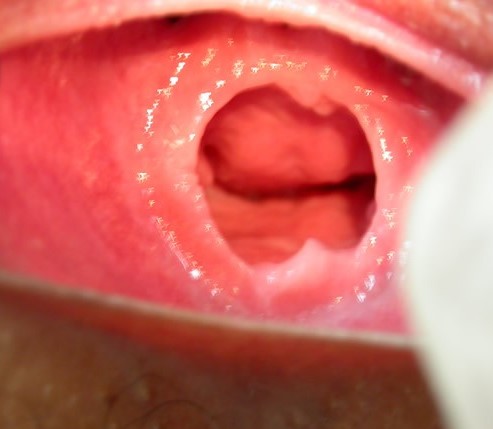

- HIMEN DE TIPO ANULAR. NOTESE EL ORIFICIO DEL HIMEN DE FORMA CIRCULAR Y DE POSICION CENTRAL EN LA MEMBRANA, CON BORDES REGULARES.